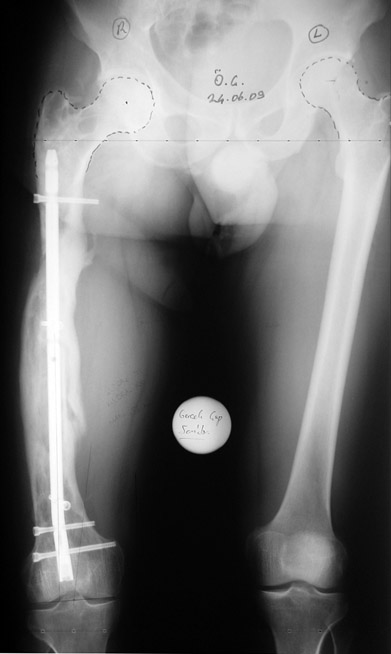

Uygun radikal debridman tüm nekrotik kemik ve yumuşak dokuların çıkartılmasını gerektirir, ve sıklıkla uzuvda instabiliteye neden olur. Kalan kemik ve yumuşak doku defektinin bir şekilde fiksasyonu ve rekonstrüksiyonu gereklidir. İlizarov’un ortaya koyduğu distraksiyon osteogenezi yöntemi, kaynamanın elde edilmesi, deformitenin düzeltilmesi, bacak boy eşitsizliğinin giderilmesi ve segmental defektlerin rekonstrükte edilmesi için başarıyla kullanılmaktadır.

Eksternal fiksatör ile geçen süre (eksternal fiksasyon indeksi), gereken distraksiyon miktarına bağlıdır ve bu süre boyunca bazı komplikasyonlarla karşılaşılabilir. Distraksiyon dönemi sona erdikten sonra, distraksiyon süresinin iki katını aşan konsolidasyon döneminde hastalar eksternal fiksatörü zorlukla tolere edebilirler. Yeterli konsolidasyon sağlanmadan eksternal fiksatör çıkartılırsa ise kırıklar, deformite ve kısalık oluşabilir. Hastanın fiksatör ile birlikte geçirdiği sürenin azaltılması ve böylece hasta konforunun ve aktivite düzeyinin arttırılması için intramedüller çivi üzerinden uzatma yöntemi uygulanmaktadır. Bu yöntemde distraksiyon dönemi sona erdiğinde kemiğin içindeki çivi statik olarak kilitlenmekte ve eksternal fiksatör çıkartılmaktadır. Stabilizasyon intramedüller çivi tarafından sağlandıktan sonra konsolidasyon dönemi gerçekleşmektedir. Bu şekilde hem eksternal fiksatörün uzun süre kalmasından hem de erken çıkartılmasından kaynaklanan komplikasyonların önüne geçilmektedir.